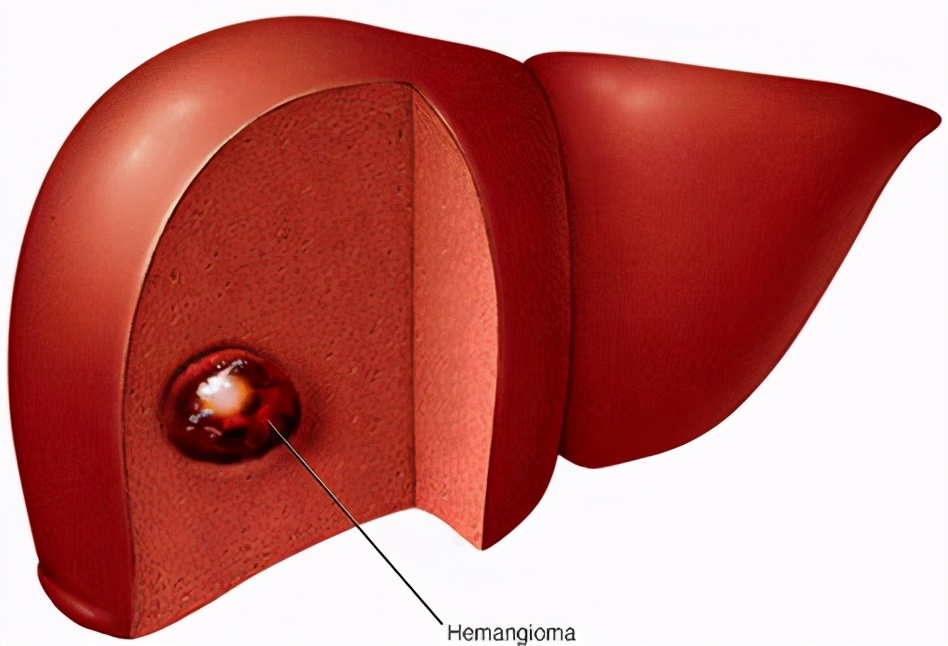

而我生长在肝脏内,是肝脏最常见的间叶组织良性肿瘤。所谓的间叶组织,通俗地说,就是指肝细胞之间或周围的组织。有人还把我切开,能看到好多海绵状的间隙,所以又称我们为“海绵状血管瘤”。

在肝脏里面,我通常是独来独往,没有伙伴,医学上叫做“单发”,当然也有“多发”的。我的身体有大也有小,通常小到数毫米,大到超过20厘米。不过,大多数小于5厘米。那些大于5厘米的,叫做“巨大血管瘤”。

在做过肝血管瘤手术的患者现场,您可以看到,我们是边界清楚的、表面上覆盖了一层薄薄的、颜色比较深的、囊状的、可能还有蒂的“瘤”。

切开来以后,可以看到红棕色的海绵状结构,有时可能会出血,还会发现有疤痕和钙化,这说明我们可能在某个时期合并过炎症。

为了看得更细,切片可以放在显微镜下观察,能够看到更细微的结构,主要是有大小不等的海绵状血管腔,腔的内表面的内皮细胞内充满着血液,可能会发现血栓、结节和钙化。